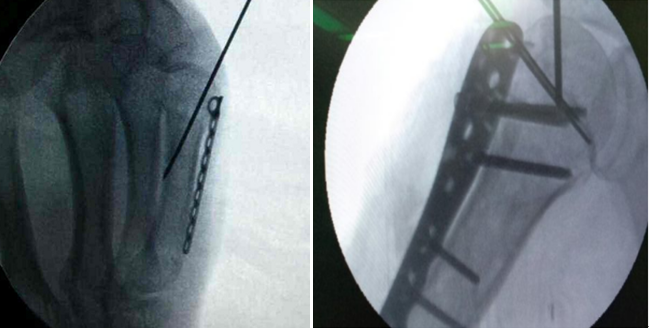

2、克氏针阻挡复位

常见于下肢髓内钉使用过程中,当髓内钉偏于一侧时,会引起下肢力线不正常,采用阻挡钉技术可以使髓内钉居中,从而复位骨折端。

7、克氏针临时固定

克氏针不仅可以对骨块进行临时固定,达到良好的复位,为置入内植入物创造环境;也可以对内固定物进行临时固定,方便下一步操作。

8、克氏针长期固定

使用克氏针代替弹性髓内钉治疗小儿以及成人骨折,同样可以取得非常好的治疗效果。